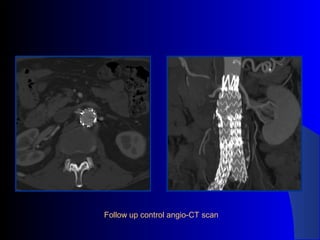

The document discusses the clinical application of the Endurant stent graft system in treating aorto-bisiliac aneurysms, detailing procedures performed on two male patients aged 72 and 73. Each patient had a history of dyslipidemia and carotid atherosclerosis, with procedures involving the bilateral bell bottom technique and the use of coils and fibrin glue. It includes pre-surgery imaging, intrasurgery angiography, and follow-up control scans to monitor outcomes.